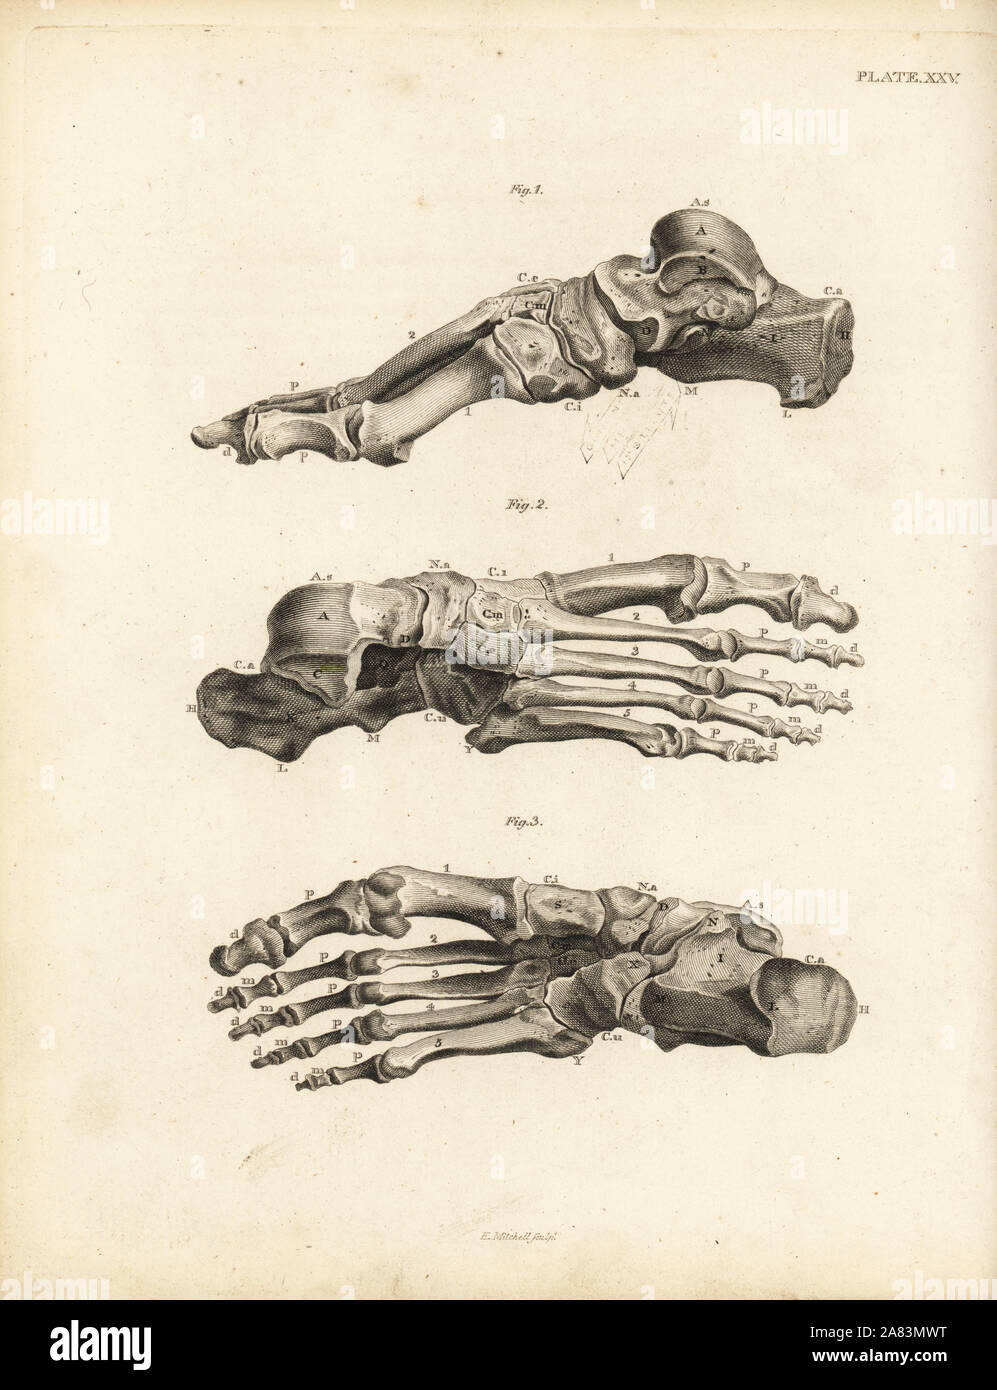

RM2A83MWT–Opinions de l'os dans le pied humain, de la cheville aux pieds. La gravure sur cuivre par Edward Mitchell après une illustration anatomique par Jean-Joseph Sue de John Barclay's une série de gravures du squelette humain, MacLachlan et Stewart, Édimbourg, 1824.

RF2BTGDWM–Les os de la Tarsal du pied sont situés dans le milieu du pied et les zones de l'arrière du pied humain, dessin de ligne vintage ou illustration de gravure.